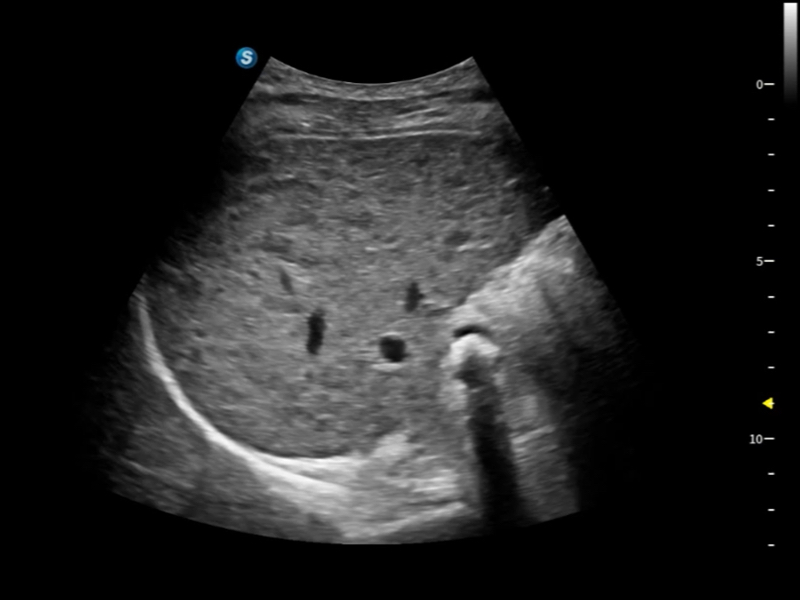

作为开立医疗全新打造的超高端旗舰超声产品,从探头抬起唤醒开启扫查到多维探头发射接收,通过先进的场成像发射、自适应聚合重建等技术,基于RF Data原始射频数据在图像生成、高端功能等方面实现突破,提供多科室综合临床解决方案。

S80 提供多样化超声成像技术,可满足不同科室的需求,在助力扫查诊断和介入治疗中发挥着重要作用。